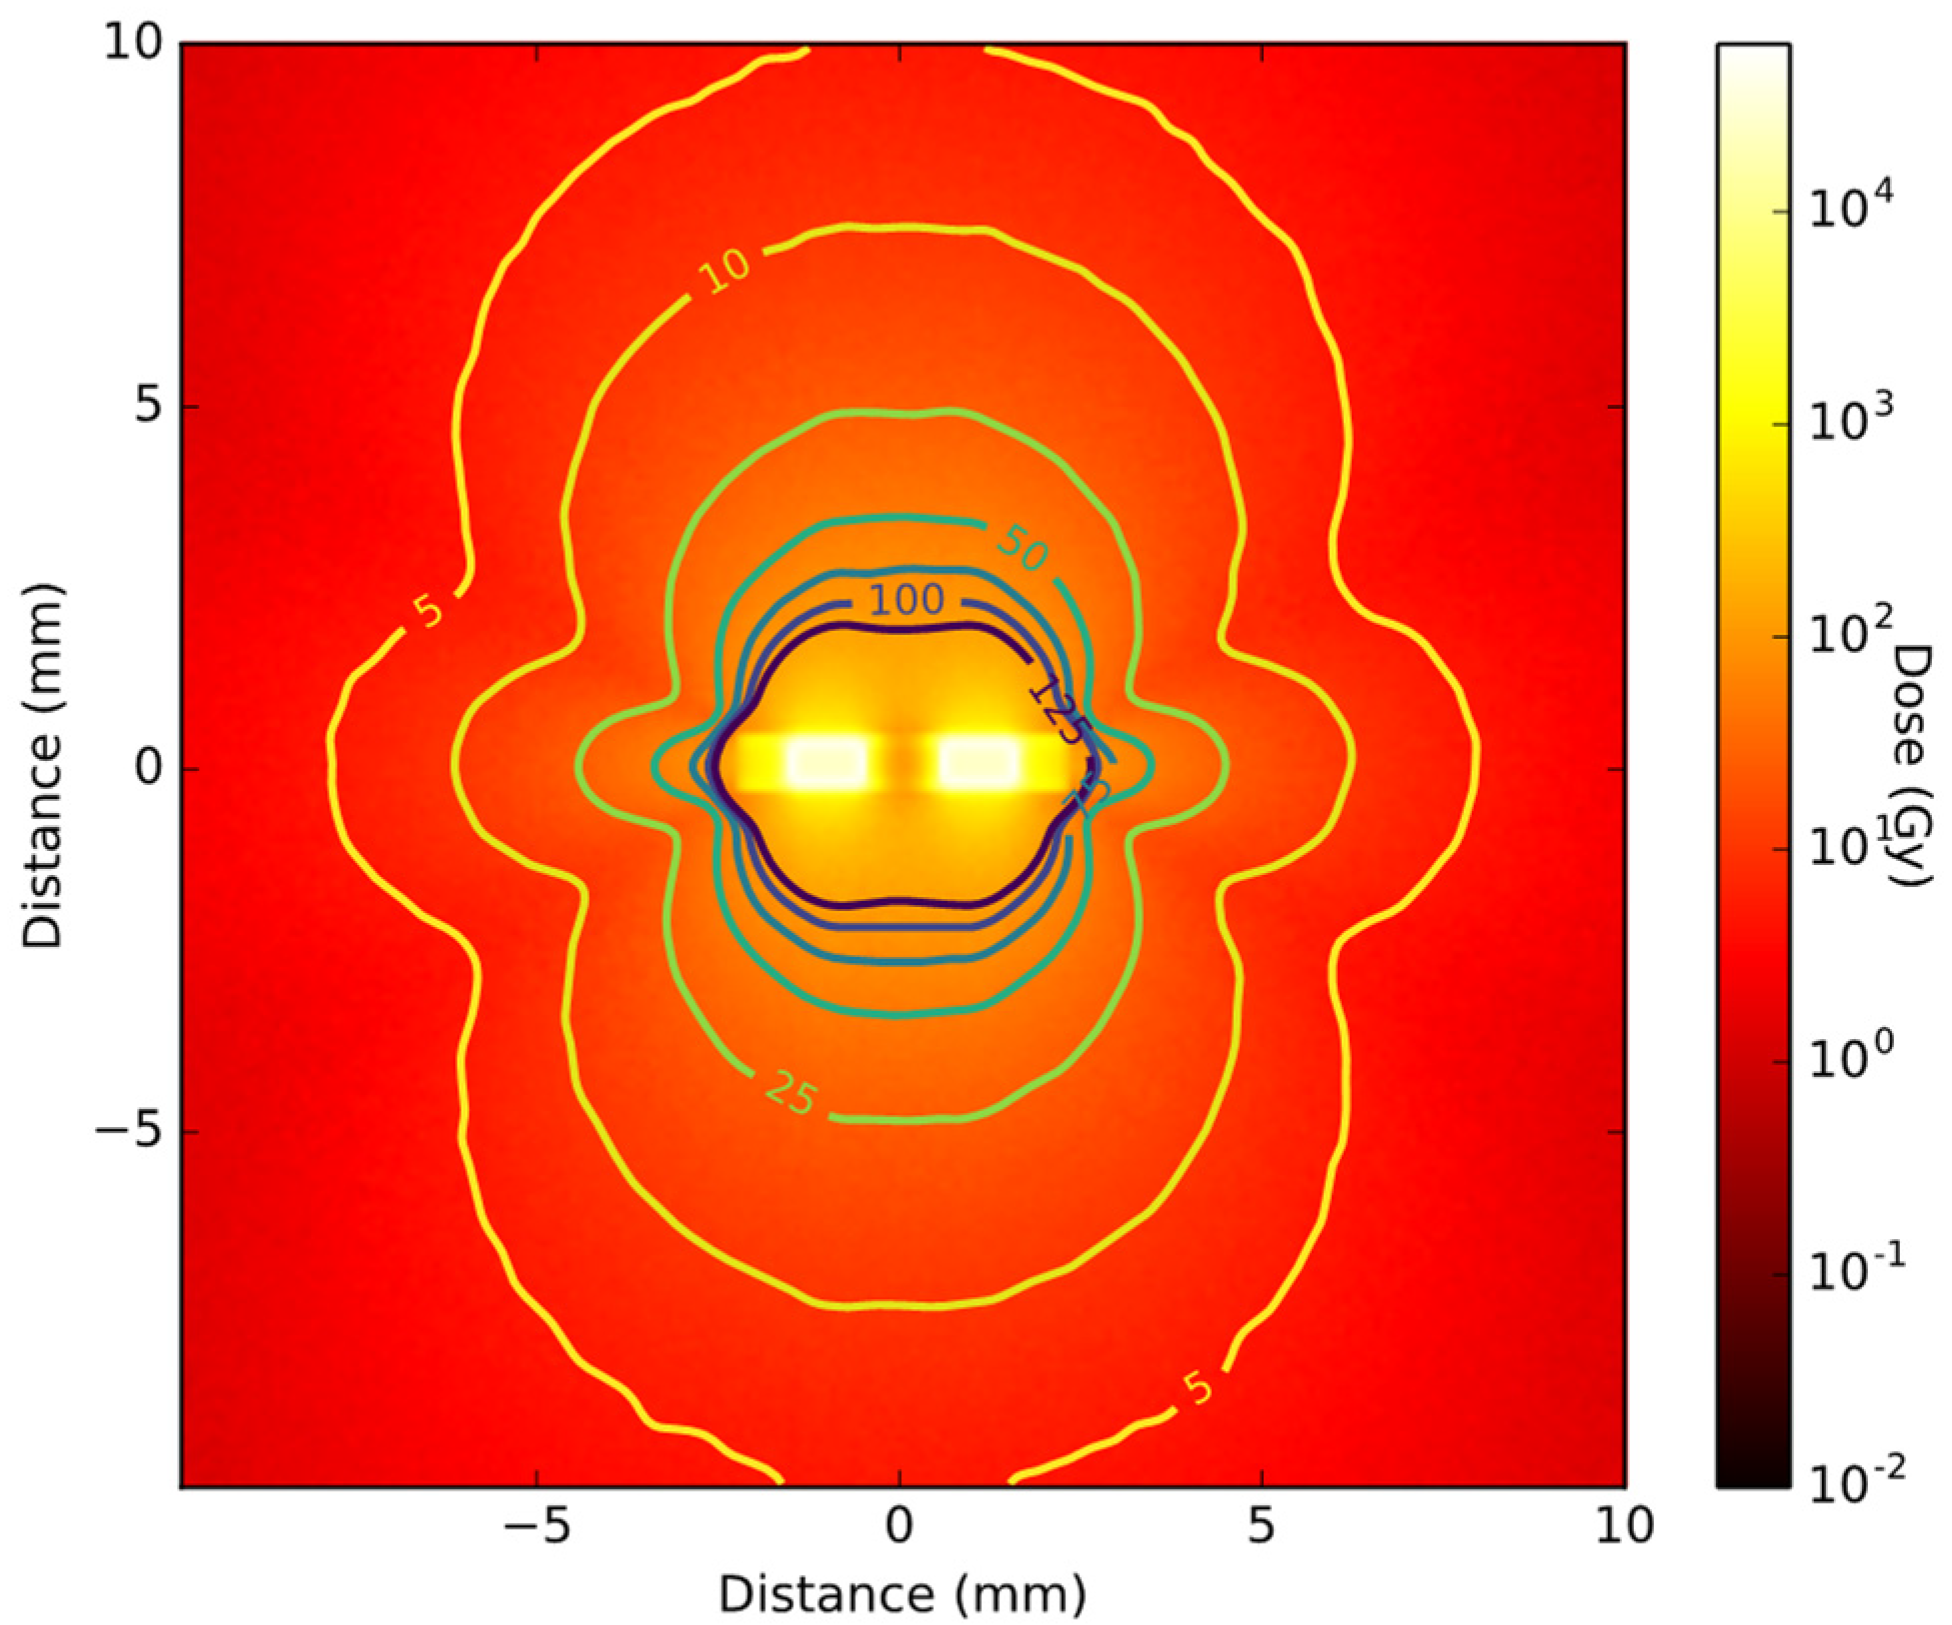

2.3. Brachytherapy Seed Simulations

3.2. Radioactive Magnetic Nanoparticle (RMNP) Seed

4. Discussion